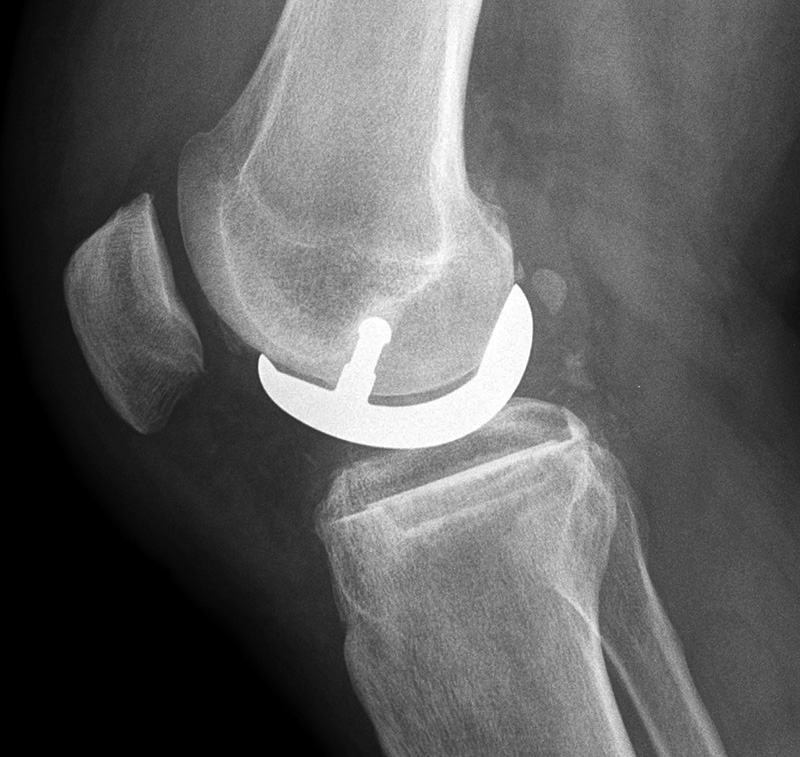

Unicompartmental knee prosthesis placed in the medial compartment (AP view) Unicompartmental knee prosthesis placed in the medial compartment (lateral view) Unicompartmental knee prosthesis placed in lateral knee compartment

Unicompartmental knee prosthesis - AP view Lateral unicompartmental knee prosthesis Lateral unicompartmental knee prosthesis

From Taljanovic, 2005 50 year-old man with lateral knee compartment degenerative osteoarthritis